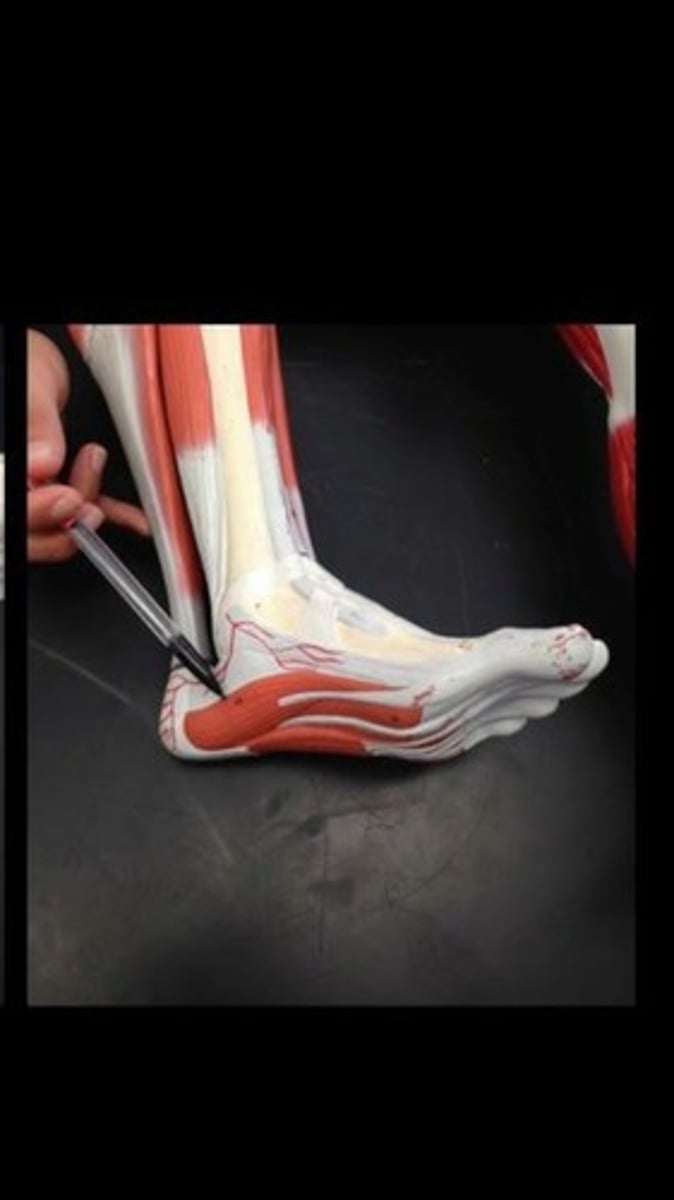

Extensor digitorum brevis of foot

Abductor digiti minimi of foot

Flexor digitorum brevis

Abductor hallucis